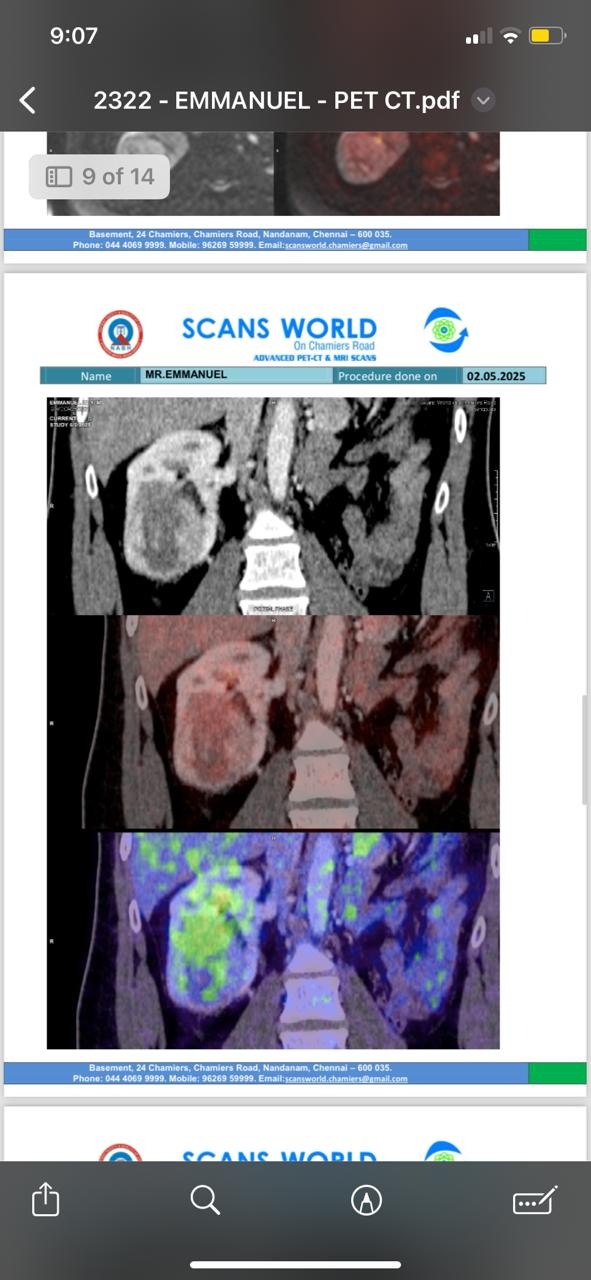

Manny was diagnosed with stage 4 clear cell renal cell carcinoma.

The cancer had come back—not only in the only kidney he has left, but also in the very space where his removed kidney once was.

And worse—it had already spread to his lungs, brain, and lymph nodes.

Doctors have confirmed this is an aggressive, recurring, metastatic cancer.

Manny has completed 17 sessions of immunotherapy and has continued treatment for his cancer. It has been a long journey filled with hospital visits, scans, uncertainty, and difficult side effects. There have been days of fatigue, pain, skin changes, and fear. Through it all, your support has carried us forward.

We recently received the results of his latest PET-CT scan, and we are grateful to share some encouraging news. The doctor described the results as very encouraging. The scan shows a further reduction in the size and activity of the tumor in his remaining kidney. The lesions in his lungs have continued to shrink, and there is no evidence of any new active disease elsewhere in his body. The brain lesion that was treated has remained stable, and several affected lymph nodes have shown continued improvement.

While this is not the end of the journey, it is a moment of hope for our family. We know there is still a long road ahead, and Manny will continue to need treatment, monitoring, and care. But today, we are thankful for progress.